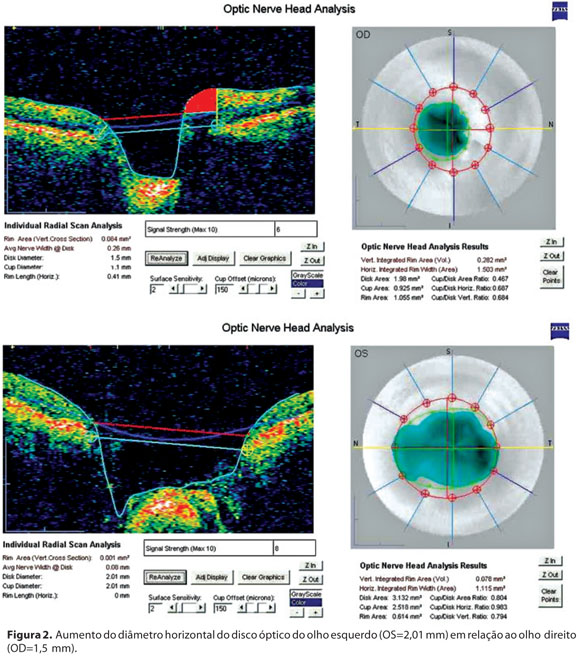

O colírio hipotensor (maleato de timolol 0,5%) foi então suspenso em ambos os olhos, e o paciente submetido a uma tomografia de coerência óptica (Stratus OCT 3), que demonstrou um leve aumento da espessura da camada de fibras nervosas no setor de 3 h no olho esquerdo, e diâmetro horizontal aumentado do disco óptico deste mesmo olho (2,01 mm) em relação ao OD (1,5 mm) (Figura 2). A PIO era de 10 mmHg nos dois olhos sem medicação.

Dentre as complicações associadas à fosseta de disco óptico, a principal delas é o descolamento seroso macular da retina, presente em aproximadamente 25% a 75% dos casos(6). A patogênese do descolamento seroso macular ainda é desconhecida. Embora as alterações vítreas sejam consideradas como as grandes responsáveis pelo mesmo, outras teorias foram postuladas, como por exemplo alterações vasculares(6-7). No presente caso, a retina do polo posterior do OE mostrava uma atrofia do epitélio pigmentar na região macular, possivelmente sequela de um descolamento seroso. Alterações campimétricas também podem estar correlacionadas às fossetas de disco óptico, como escotomas arqueados e paracentrais, que não tendem a progredir nos exames subsequentes(3-4). Exames de imagem, como a tomografia de coerência óptica, têm sido utilizados, não só no diagnóstico, como também no acompanhamento do descolamento seroso macular(9). Além de alterações retinianas, é possível observar na tomografia de coerência óptica algumas alterações estruturais no nervo óptico compatíveis com fosseta. Dentre estas alterações, pode-se observar um aumento no tamanho do disco óptico, seja no sentido horizontal ou vertical, o que depende da localização da fosseta, e diminuição da espessura da camada de fibras nervosas no local correspondente à fosseta(10).